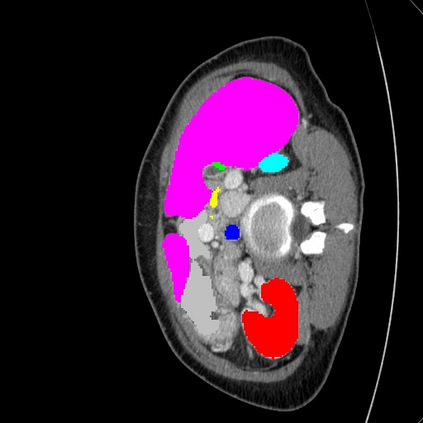

Transformers have made remarkable progress towards modeling long-range dependencies within the medical image analysis domain. However, current transformer-based models suffer from several disadvantages: (1) existing methods fail to capture the important features of the images due to the naive tokenization scheme; (2) the models suffer from information loss because they only consider single-scale feature representations; and (3) the segmentation label maps generated by the models are not accurate enough without considering rich semantic contexts and anatomical textures. In this work, we present CASTformer, a novel type of generative adversarial transformers, for 2D medical image segmentation. First, we take advantage of the pyramid structure to construct multi-scale representations and handle multi-scale variations. We then design a novel class-aware transformer module to better learn the discriminative regions of objects with semantic structures. Lastly, we utilize an adversarial training strategy that boosts segmentation accuracy and correspondingly allows a transformer-based discriminator to capture high-level semantically correlated contents and low-level anatomical features. Our experiments demonstrate that CASTformer dramatically outperforms previous state-of-the-art transformer-based approaches on three benchmarks, obtaining 2.54%-5.88% absolute improvements in Dice over previous models. Further qualitative experiments provide a more detailed picture of the model's inner workings, shed light on the challenges in improved transparency, and demonstrate that transfer learning can greatly improve performance and reduce the size of medical image datasets in training, making CASTformer a strong starting point for downstream medical image analysis tasks.